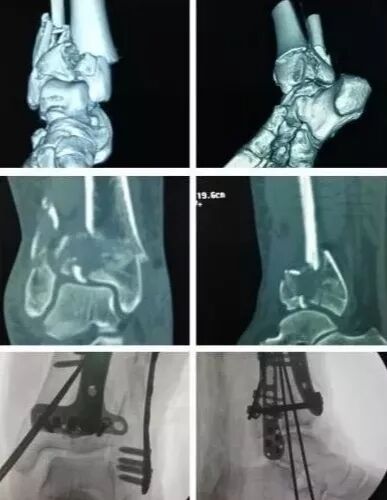

7)胫骨远端(pilon,踝部)

图片

• pilon骨折,高能损伤,6-8h肿胀未形成,可以急诊做,手术时间<3小时。

• 10-14天,分步延期手术策略。

• 踝部骨折手术时机同样取决于皮肤条件。

8)足部骨折(距骨,跟骨,跖骨等)

高能损伤导致的距骨骨折并脱位,建议急诊做。